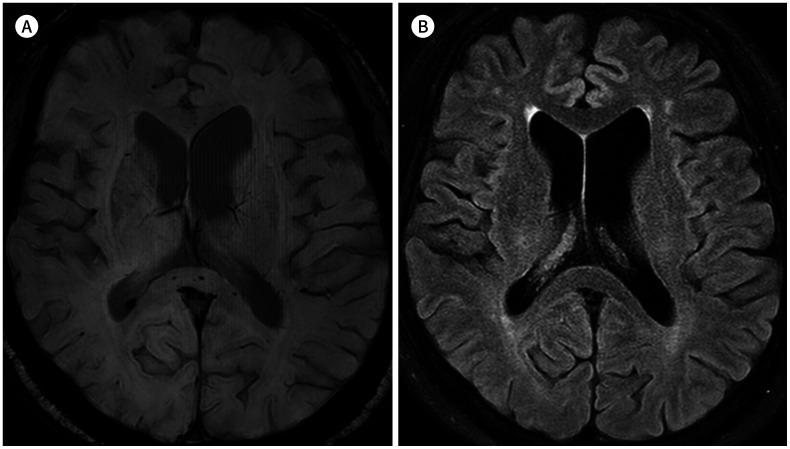

Microbleeds in the Corpus Callosum in Anoxic Brain Injury.

This study was performed to evaluate the relationship between callosal microbleeds and anoxic brain injury.

The prevalence of cerebral microbleeds in the patient group was 29.6%, which was significantly higher than that in the control group at 3.7% ( = 0.012). All cerebral microbleeds in the patient group were in the corpus callosum. Compared with the callosal microbleed-absent group, the callosal microbleed-present group showed a tendency of good prognosis (6/8 vs. 11/19), fewer typical MRI findings of anoxic brain injury (2/8 vs. 10/19), and more cardiopulmonary resuscitation (6/8 vs. 12/19), although these differences did not reach statistical significance ( = 0.35, = 0.19, and = 0.45, respectively).

Callosal microbleeds may be an adjunctive MRI marker for anoxic brain injury.